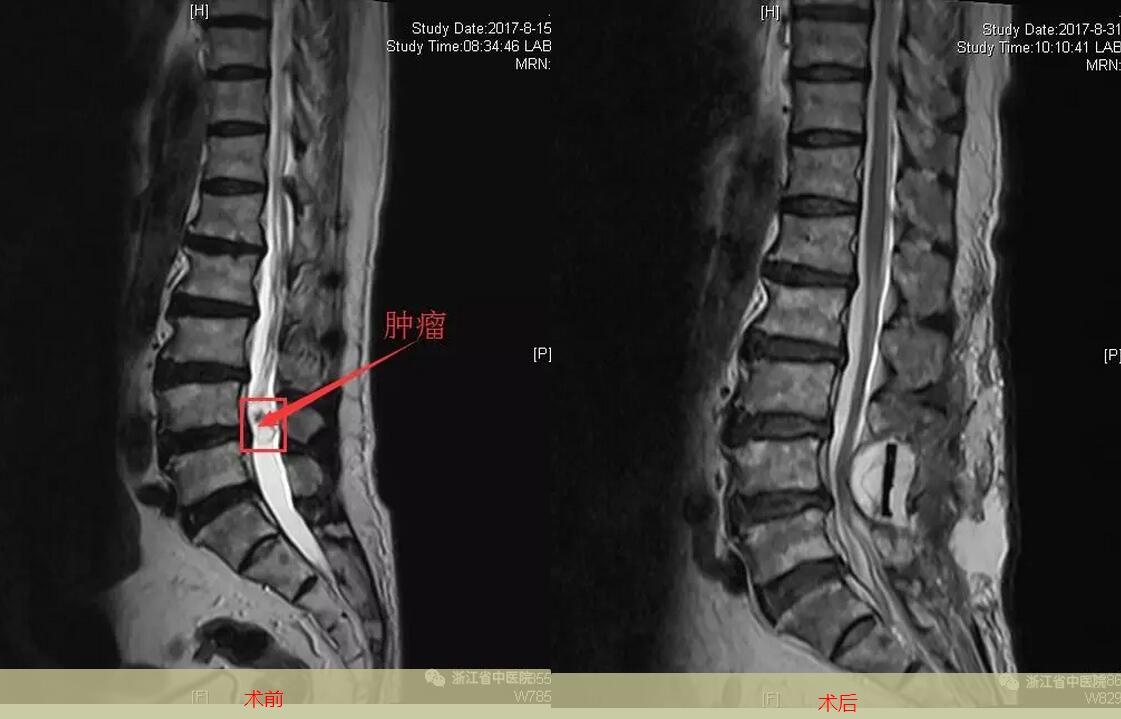

8月10日,患者来到浙江省中医院下沙院区就诊,接诊的是神经外科张铁辉副主任医师,仔细询问病情后,为其开了MRI检查,显示为腰4-腰5间隙椎管内占位病变,直径约3cm。入院后,患者病情经过多学科联合分析讨论,诊断为腰椎管内肿瘤,手术指征明确,建议尽早手术。团队为患者制定个体化手术方案,以最小创伤获取最大收益,尽最大程度保留神经脊髓功能。最终确定了对徐老伯进行腰椎管肿瘤切除术+椎体固定术+人工椎板重建的手术方案。

8月17日手术由神经外科张铁辉副主任医师和骨科李战春主任医师操作,神经外科黄李法主任医师全程指导,成功对徐老伯进行了肿瘤切除。手术当中发现,肿瘤巨大,多根马尾神经包绕肿瘤,部分马尾神经穿行于肿瘤内,在显微镜下,对穿行于肿瘤中的马尾神经进行仔细梳理,完整切除肿瘤,马尾神经及终丝无损伤,水密缝合硬脊膜,人工椎板重建椎管,按解剖层次进行复位,钉棒对椎体进行固定,完全达到脊柱的力学要求。